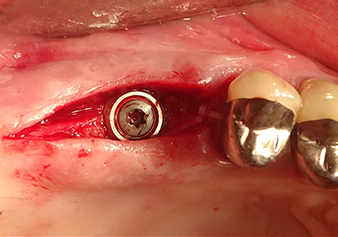

49-летняя пациентка, некурящая и не имеющая ничего примечательного в общей истории болезни, была направлена в нашу хирургическую стоматологическую клинику для хирургического удаления зуба 16 и последующей имплантации. После удаления зуба пациентка перенесла синусит в легкой форме, в результате чего мы сначала выждали шесть месяцев перед проведением операции. Остаточная высота кости при запланированном положении имплантата составляла 3-4 мм (рис. 1 и 2).

После атравматичной подготовки слизисто-костной оболочки, положение импланта было определено с помощью инструмента I1, далее была проведена подготовка поверхности - до тех пор, пока не возникло первичное сопротивление. Пьезохирургические инструменты были использованы в движении вверх и вниз без оказания давления. Пьезоэлектрическая вибрация создавала необходимую кавитацию.

Затем, с помощью инструмента I2A (диаметр 2,0 мм), дно пазухи перфорировалось периодически и в минимально возможном диапазоне. Этот специфический пьезохирургический метод гарантирует, что мембрана Шнейдера не будет повреждена. При использовании Z25P, мембрана уже была слегка приподнята охлаждающей жидкостью, подаваемой через наконечник инструмента (рис. 3). Во избежание высокого давления в ложе имплантата, количество охлаждающей жидкости составляло не более 50%.